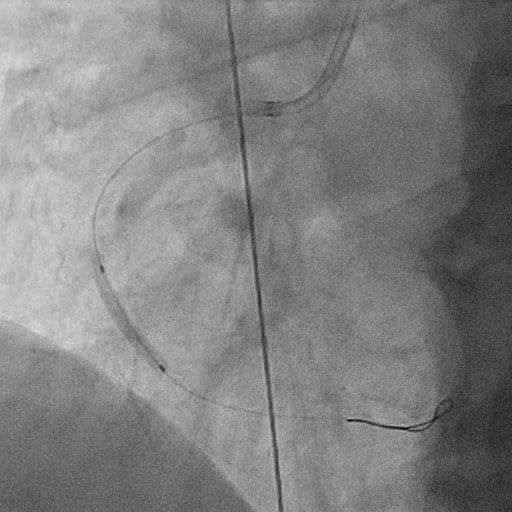

Wie läuft eine Stent-Implantation ab?

Die Stent-Implantation läuft wie folgt ab:

- Zugang über Arm- oder Leistenarterie

- Herzkatheter bis zu den Koronarien

- Ballon-Dilatation der Engstelle

- Platzierung des Stents

- Nachsorge mit Blutverdünnern (ASS + P2Y12-Hemmer)

Das nachfolgende Bild zeigt eine Ballon-Dilatation bzw. eine Aufdehnung des verengten Herzkranzgefäßes. Ein Katheter mit einem kleinen Ballon an der Spitze ist in das verengte Gefäß eingeführt worden. Der Ballon ist aufgeblasen, um die Ablagerungen an die Gefäßwände zu pressen und das Gefäß so zu weiten.

Herzkatheter in Aktion: Einblick in die Gefäße

Um den Ablauf einer Stent-Implantation besser zu veranschaulichen, zeigen wir Ihnen hier, wie die Herzkranzgefäße vor und nach der Behandlung aussehen. Die Aufnahmen stammen aus der Live-Durchleuchtung während des Eingriffs und geben Ihnen einen echten Einblick in die Funktionsweise des Herzkatheters. Diese Aufnahmen verdeutlichen, wie der Stent das Gefäß sofort entlastet und die Durchblutung wiederherstellt.

1. Das verengte Gefäß (vor der Behandlung)

In diesem ersten Video sehen Sie das Herzkranzgefäß vor dem Eingriff. Die Verengung (Stenose) behindert deutlich den Blutfluss zum Herzmuskel.